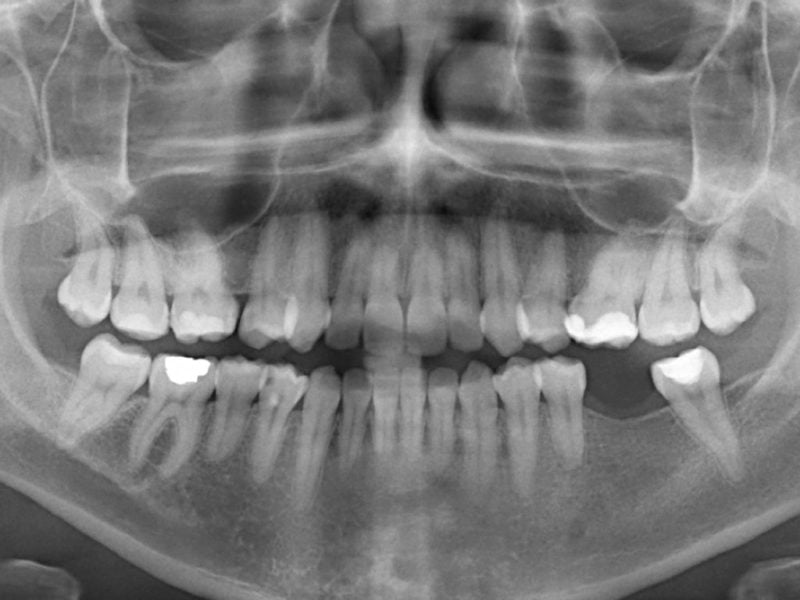

Dr. LINO VINICIUS Country: Portugal Gallery Patient’s Data: Age: 51 Sex: Female Smoker: No Pathologies: None Hygenic state: Good Alergies: None The loss of a single posterior tooth can cause the anatomical readaptation of tissues and it may lead to the loss of other teeth. This lady came to our office with one tooth missing, […]

Dr. FRANCESCO LERARIO Country: Italy Gallery Patient’s Data: Age: 44 Sex: Male Smoker: Yes Pathologies: None Hygenic state: Bad Alergies: None Immediate load rehabilitation on 5 implants with resin prosthesis. The patient came to our attention presentng an edentulous upper arch. He had an inappropriate total removable prosthesis that made him demotivated. Several implantologists had […]

Dr. LINO VINICIUS Country: Portugal Gallery Patient’s Data: Age: 39 Sex: Female Smoker: No Pathologies: None Hygenic state: Good Alergies: None This youg lady came to our office with a compromised tooth, we inserted an implant from the EV line and we waited for 4 months for healing. During healing we inserted the PEEK healing […]